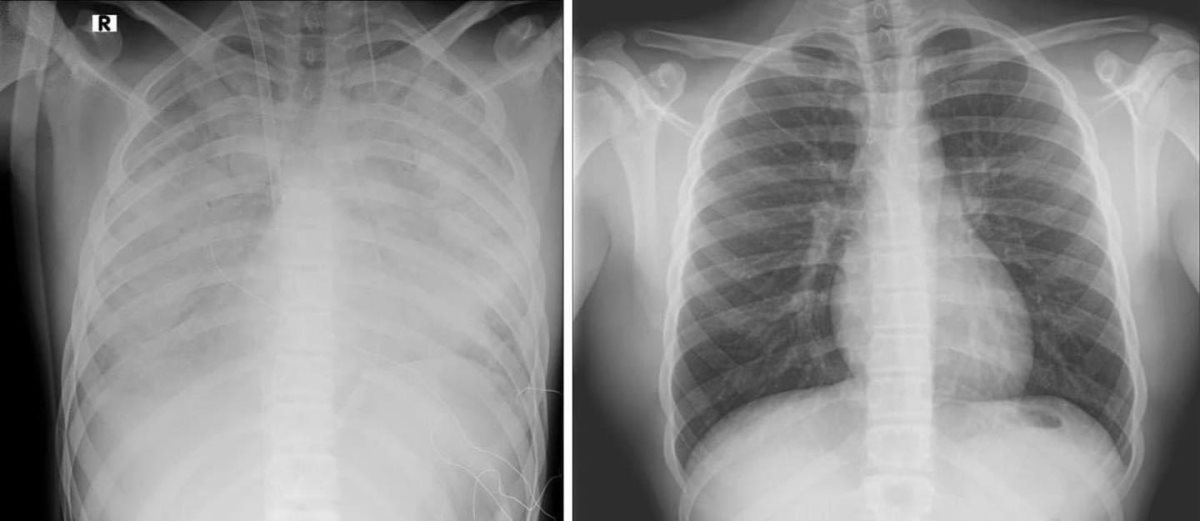

נער בן 16 מאושפז במרכז שניידר במצב קשה עם קריסה של הריאות לאחר שימוש בסיגריות אלקטרוניות. הנער הובהל ליחידה לטיפול נמרץ לב, שם הוא מאושפז בהכרה ומחובר למערכת האקמו, המחליפה את פעילות הלב והריאות - כך מפרסמים הבוקר כתבי אתר ויינט, רענן בן צור וגד ליאור.

הנער הועבר למרכז שניידר מבית החולים קפלן, לאחר שריאותיו קרסו. מבירור רפואי מקיף שערכו בבית החולים קפלן עלה כי מצבו הידרדר כתוצאה מעישון של סיגריות אלקטרוניות.